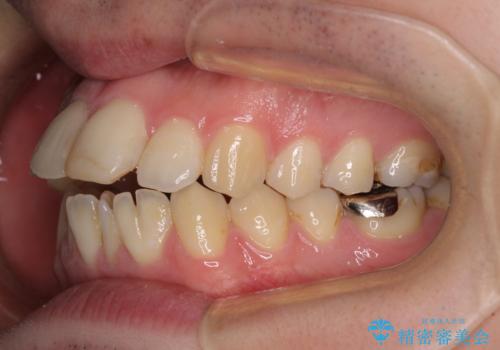

しゃくれて口が閉じられない ワイヤー装置での抜歯矯正

- 口がうまく閉じられないとのことで来院された患者様です。

上下唇をしっかり合わせようとすると、顎先が前方に突出してしまうほど口が閉じにくい状態でした。

口元の突出感を改善するために上下左右の第一小臼歯4本を抜歯し、ワイヤー装置にて矯正治療を行うこととしました。

また、上下前歯は舌の突出癖による開咬となっていたため、舌のトレーニングを徹底するよう指示しました。